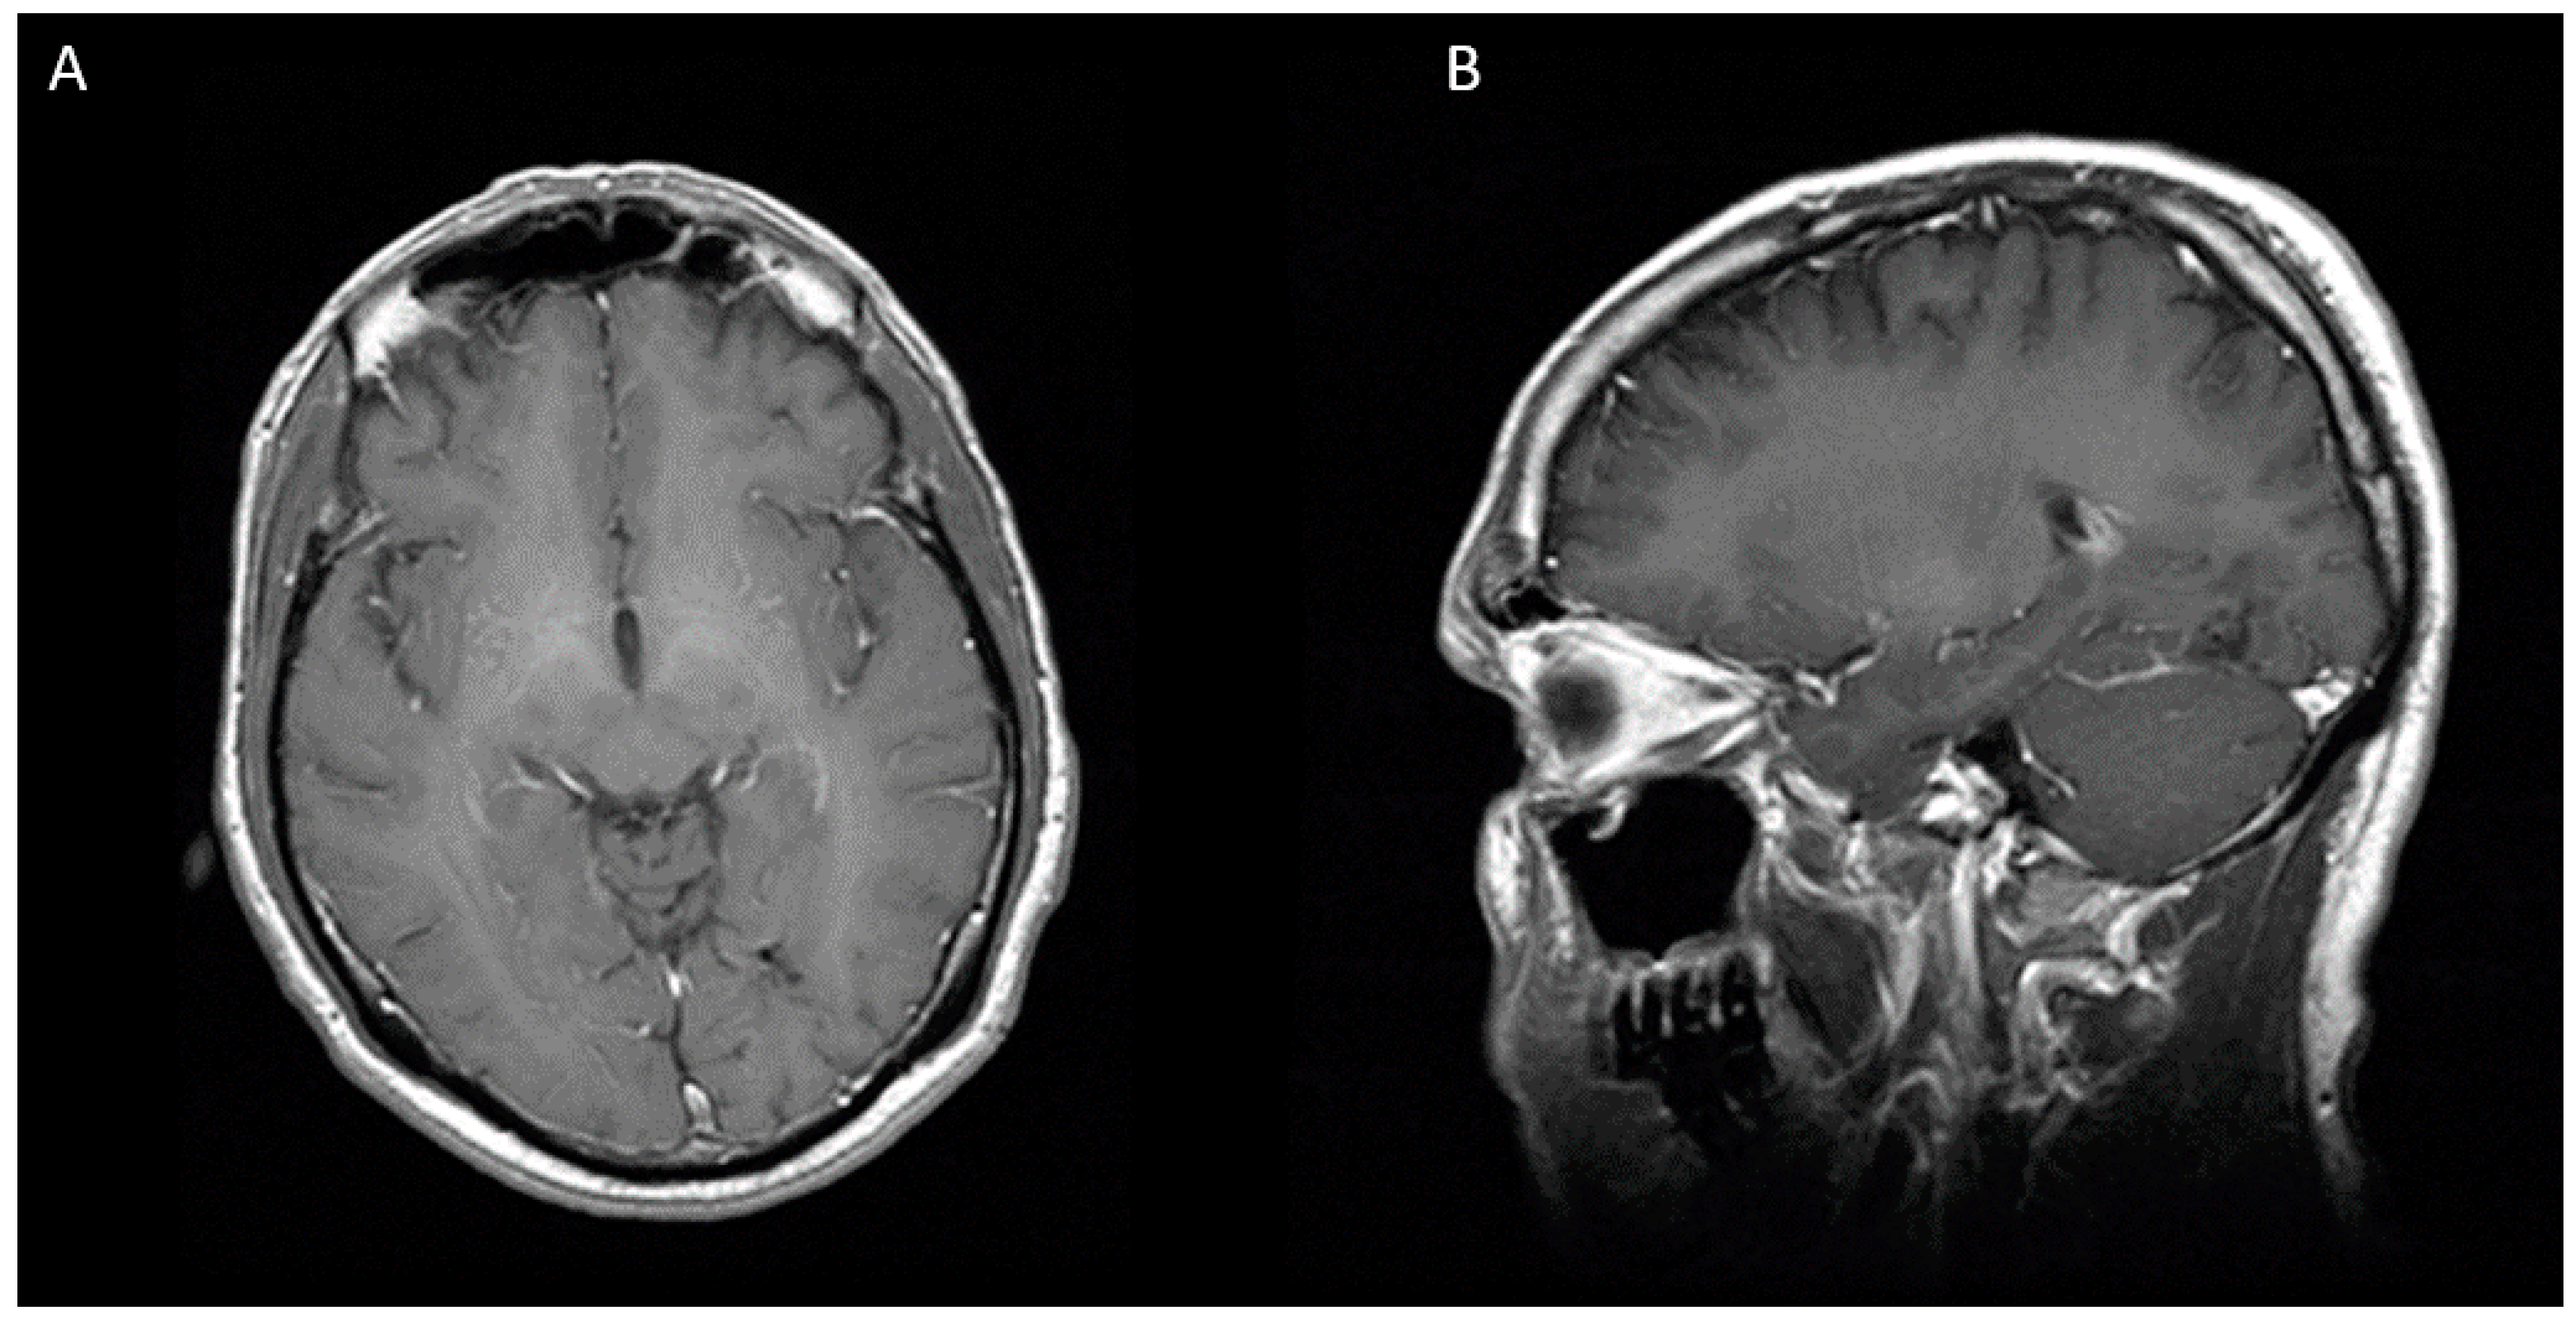

Cureus Cerebral Abscess Due to Nocardia beijingensis Associated With HIV Case Report and Mini

From www.cureus.com

Cureus Cerebral Abscess Due to Nocardia beijingensis Associated With HIV Case Report and Mini Brain Abscess Aids  An abscess can also keep blood from flowing to parts of your brain.   how is a brain abscess treated?  cerebellar or brain stem abscesses are often indication for posterior fossa craniotomy due to the high risk of brain herniation.[3,25]. A brain abscess is a medical emergency that requires immediate attention.   nocardia is an important cause of brain. Brain Abscess Aids.

From www.researchgate.net

(PDF) Cerebral Abscess Due to Nocardia beijingensis Associated With HIV Case Report and Mini Review Brain Abscess Aids    the diagnosis of brain abscess requires a high index of suspicion since it can have a subtle presentation.   how is a brain abscess treated?   clinical signs of increased intracranial pressure (eg, papilledema, cushing triad [hypertension, bradycardia, and irregular.   the diagnostic approach to a patient with hiv/aids and a brain mass should be stepwise, considering host factors,.. Brain Abscess Aids.